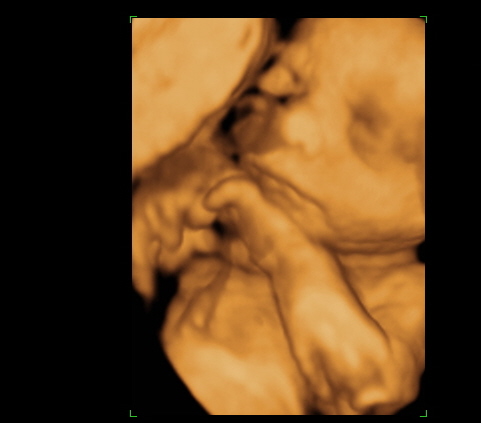

Dobok gyorsan pár képet, aztán húzok aludni.

Bölcsis szülinap:

Így kidőltek utána

Ilyen kisegér tortája volt

(Amilyen jól nézett kis, annyira baromi rossz volt

)

A végére pedig egy össznépi